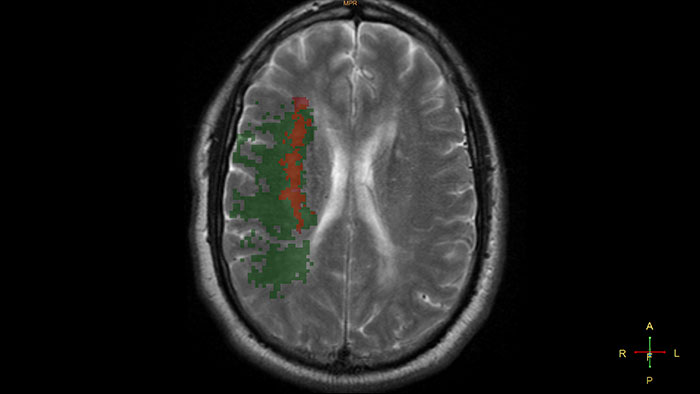

Gain an optimized view of the body’s most complex organ

Supports the visualization of brain images for the evaluation and monitoring of changes across multiple time points. The application performs automatic registration between studies and provides semi-automatic segmentation and editing tools for volumetric measurement of brain lesions.

Benefits